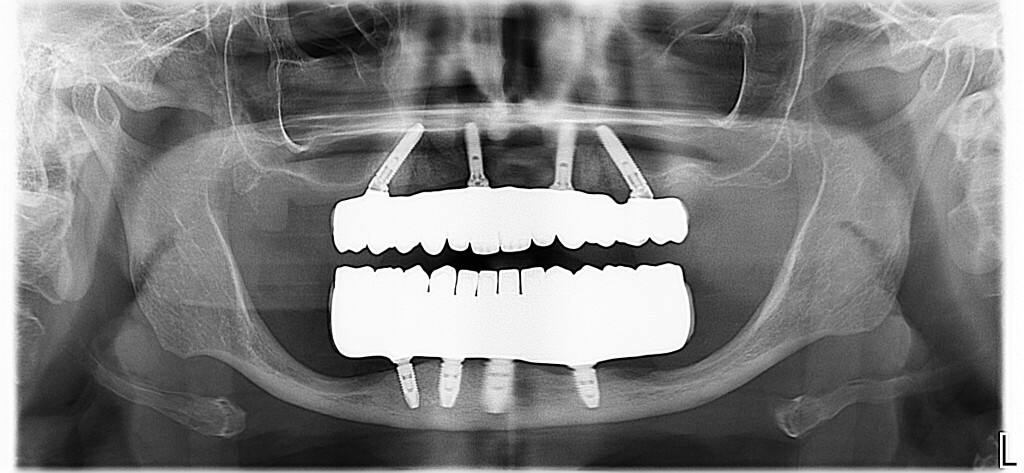

e il lavoro finito.

Panoramica

Oggi siamo a 3 anni di follow-up e la paziente è una delle nostre principali sostenitrici, non perde occasione di farci pubblicità e di portarci altri pazienti.